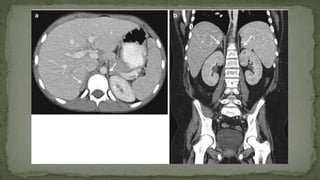

➢ The shape of the adrenal gland on CT cuts is variable, with a linear, inverted V shape

being commonest on the right and a triangular or Y shape commonest on the left.

➢ Craniocaudal extent is less than 4 cm.

➢ Limb thickness is usually less than 1 cm.